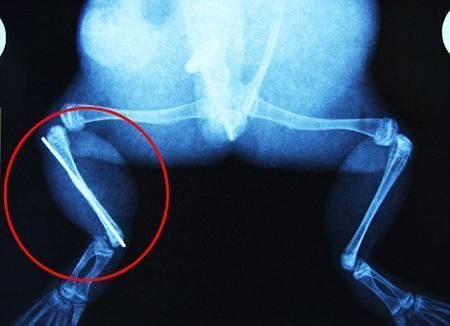

環(huán)球網(wǎng)4月2日報(bào)道 據(jù)《每日郵報(bào)》報(bào)道,上個(gè)月,南非大牛蛙布魯萊的右小腿被鄰居家的一只狗咬到,導(dǎo)致粉碎性骨折,現(xiàn)在經(jīng)過2個(gè)小時(shí)的手術(shù),它的斷腿已經(jīng)被接上,它也因此成為有史以來第一只通過外科手術(shù)用鋼針接上斷腿的青蛙。

布魯萊的主人,居住在南非約翰內(nèi)斯堡附近的62歲的安妮·米恩斯說:“我對這只青蛙如此關(guān)心,人們一定認(rèn)為我瘋了,但是我無法眼睜睜看著它那么痛苦。青蛙因其靈活的腿腳而著稱,一想到布魯萊的腿里要留下一個(gè)薄金屬片,我就感到心痛。然而我知道,如果不進(jìn)行手術(shù),布魯萊以后就沒辦法動(dòng)彈了。因此我匆匆趕到獸醫(yī)那里,央求他給這只可憐的青蛙動(dòng)手術(shù)。這位獸醫(yī)整天救助小貓小狗,他很難理解為什么我這么擔(dān)心一只青蛙,但是最終他還是答應(yīng)了給布魯萊做手術(shù)。手術(shù)后是幾個(gè)小時(shí)的焦急等待,我們希望它能快快蘇醒過來。不過現(xiàn)在它的傷口已經(jīng)愈合,又能在花園里跳來跳去了。X光照射顯示,它會(huì)恢復(fù)的跟以前一樣!

野生生物專家安妮經(jīng)常為學(xué)校寫教材,她認(rèn)為這是人類第一次通過手術(shù)給一只青蛙接斷腿。在手術(shù)開始階段,獸醫(yī)把少量給狗用的麻醉藥注入到這只青蛙體內(nèi),讓它失去知覺。然后他在布魯萊的斷腿上切開一個(gè)小口,把一根小鋼針植入腿里。最后獸醫(yī)給它縫了9針,把切口縫合在一起。僅僅幾周后,布魯萊就能在安妮家附近活動(dòng)了。這只青蛙大約已有25歲,主要以嚙齒動(dòng)物、蛇和其他青蛙為食。布魯萊所屬的牛蛙種群正在不斷減小,目前只能在非洲南部的濕地里才能看到這種青蛙。